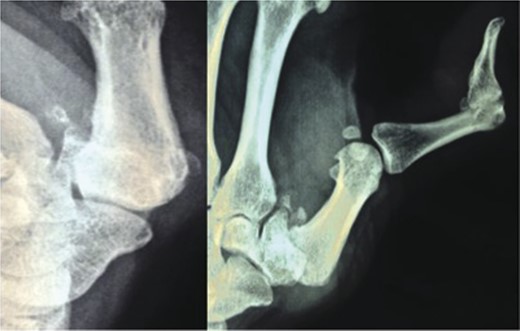

We further evaluated the patient using radiographs of the shoulder (Fig. 2) and thumb (Fig. 3) which confirmed our suspicion of neuropathic arthropathy. To exclude Milwaukee shoulder as a cause of the severe changes observed on the shoulder radiograph, we performed an MRI of the shoulder which revealed an intact rotator cuff (Fig. 4). Further, due to the associated neurological symptoms in the left upper limb, we performed an MRI of the cervical spine (Fig. 5) to identify any underlying neurological pathology. This MRI revealed a multi-level cervical syringomyelia.

Posterio-anterior and oblique photograph of the left thumb showing severe arthritic changes in the first CMC joint with severe reduction in joint space, volar subluxation, subchondral sclerosis, osteophytic changes and loose bodies.